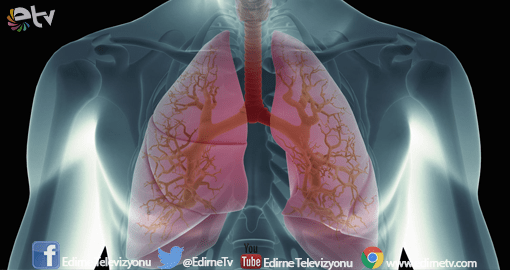

Trakya Üniversitesi (TÜ) Tıp Fakültesi Hastanesi Göğüs Hastalıkları Anabilim Dalı Öğretim Üyesi Prof. Dr. Gündeniz Altıay'ın, sigaranın sebep olduğu hastalıkların başında akciğer kanserinin geldiğini ifade etti.

Hastalığın akciğer dokularında bulunan anormal hücrelerin kontrolsüz çoğalmasıyla ortaya çıktığını dile getiren Altıay, akciğer kanserinin dünya genelinde çok sık görülen bir hastalık olduğunu vurguladı.

Akciğer kanserinin hem gelişmiş hem de gelişmekte olan ülkeler için önemli bir ölüm nedeni olduğunu aktaran Altıay, konuşmasına şöyle devam etti:

“Dünya genelinde hem kadınlarda hem erkeklerde kansere bağlı ölümlerin en sık görülen türü akciğer kanseridir. Tüm kanser ölümlerinin yüzde 20'si akciğer kanserine bağlıdır. Bu sayı her yıl meme, kolon ve prostat kanserinden dolayı kaybedilen hasta sayısı toplamından daha yüksektir. Türkiye'de, akciğer kanserinin görülme sıklığı erkeklerde 100 binde 75, kadınlarda ise 100 binde 10. Yaklaşık olarak her yıl 30 bin yeni akciğer kanseri vakası görülmekte.

Daha önceki yıllardan kalan hastalarla birlikte yılda 60 bin akciğer kanseri hastası Türkiye'de tedavi görüyor. Akciğer kanserindeki en önemli sorunlardan biri, hastalık bulgu verdiğinde semptomların ilerlemiş durumda olması. Akciğer geniş ve esnek bir organ. Tümör orada büyüyene kadar kendisini gizleyebiliyor. O yüzden olgularımızın yüzde 75'i bize yaygın evrede geliyor. Sadece yüzde 15'i cerrahiyle çıkarılıp tedavi edilme şansı bulabiliyor.”

Erken tanının hastalığın tedavisi ve yaşam süresinin uzamasında önemli bir faktör olduğunu belirten Altıay, Akciğer kanserinde hastalara farklı tedavi yaklaşımlarının da uygulandığını aktardı. “Cerrahi dönemini kaçırmış hastalarda temel yaklaşım kemoterapi ve radyoterapi.” diyen Altıay, şunları kaydetti:

“Akciğer kanseri dokusunda bir takım genetik moleküller ve belirteçlere bakılarak, bunlara odaklı tedaviler uygulanmaya başlandı. Bu tedavilerle daha uzun yaşam süreleri sağlanmakta. Bu yöntemde üniversitemizde ve Türkiye'de yapılmakta. Tabii bu tüm hastalar için mümkün olmuyor. Yaklaşık yüzde 20'sinde bu belirteçler pozitif oluyor ve medikal onkoloji uygulanabiliyor. Evre 1'de cerrahi tedaviyle yıllık sağ kalım yüzde 60'larda. Erken tarama çalışmalarında bir santimetrenin altındaki nodüller erken dönemde alınırsa 10 yıllık yaşam süreleri yüzde 80'leri aşıyor. Akciğer kanserinde yüzde 100'ü yakalamak kolay değil. Cerrahi tedavi şekli çok büyük oranda başarıya ulaşıyor diyebiliriz.”